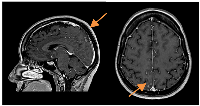

Figure 3

CE MRI response evaluation after 3 cycles of T-DXd.

Right parietal lesion was residual and pachymeningeal infiltration was not found (arrows).

A slow but steady neurological improvement was achieved, with full autonomy recovery after only three cycles of T-DXd. Response evaluation with CE and neuraxis MRI showed excellent disease response: right parietal lesion was residual and pachymeningeal infiltration was not found; LMC was noticeably reduced (in extension and intensity) (Figures 3 and 4). Toraco-abdominal and pelvic CT (TAP-CT) was systematically negative for new distant secondary disease.